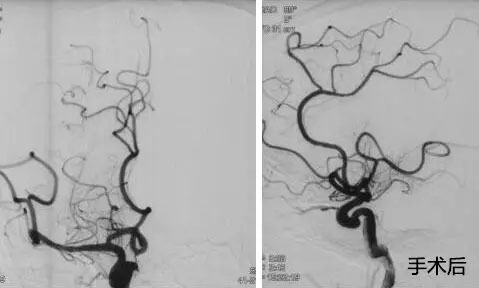

▲ 患者取栓前后DSA造影图

10:00am,患者被送入手术室,全麻下行全脑血管造影示:右侧颈内动脉处血流完全闭塞,血栓位于右侧颈内动脉T型分叉部,其他血管代偿不好,必须及时取栓干预。将微导管、微导丝送达血栓远瑞,微导管、微导丝到位后,成功释放支架,多次抽吸+支架拉栓,历时三个小时,取出大量血栓,患者血管达到2B级开通,血管恢复了供血。术后,转入九楼ICU。目前患者状态平稳,正在康复中。